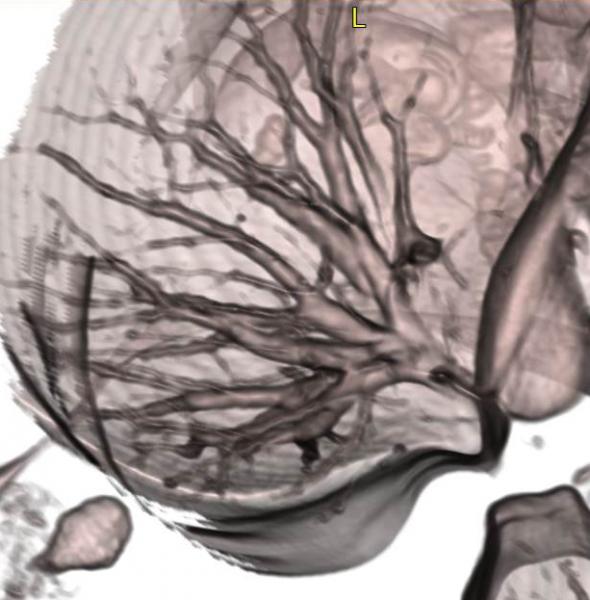

Planmed Verity is designed to find subtle extremity fractures during the first visit to the clinic. Planmed Verity Extremity Scanner provides fast, 3-D imaging at the point of care. It is intended for pre- and postoperative imaging, and it has better resolution and patient adaptability and uses a significantly lower dose of radiation than full-body computed tomography (CT). Planmed Verity also allows for weight-bearing imaging of the extremities.